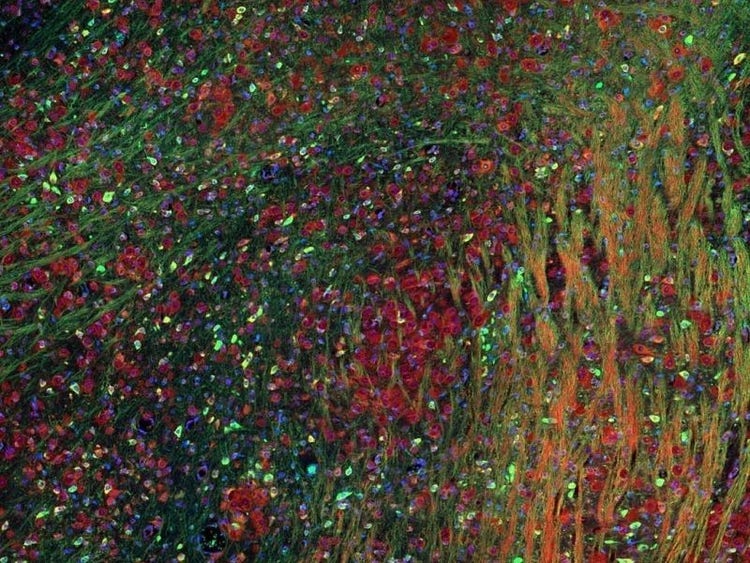

Fluorescence imaging of a mouse brain

これらの画像は一つひとつが独立した拡大画像に見えますが、すべて合わせると、蛍光イメージングで撮影されたマウスの脳の画像が形作られます。

イギリスの科学者、George G. Stokes卿は、蛍石に紫外線を当てると蛍光を発することを最初に発見し、「蛍光」という用語を作りました。Stokes卿は、蛍光は励起光よりも波長が長いことに気づき、今日では、この現象はストークスシフトとして知られています。蛍光顕微鏡法は、自然のまま(一次蛍光または自家蛍光と呼ばれます)か、蛍光を発することのできる化学物質で処理した場合(二次蛍光として知られています)かのいずれかで蛍光を発することのできる物質を研究するための優れた方法です。